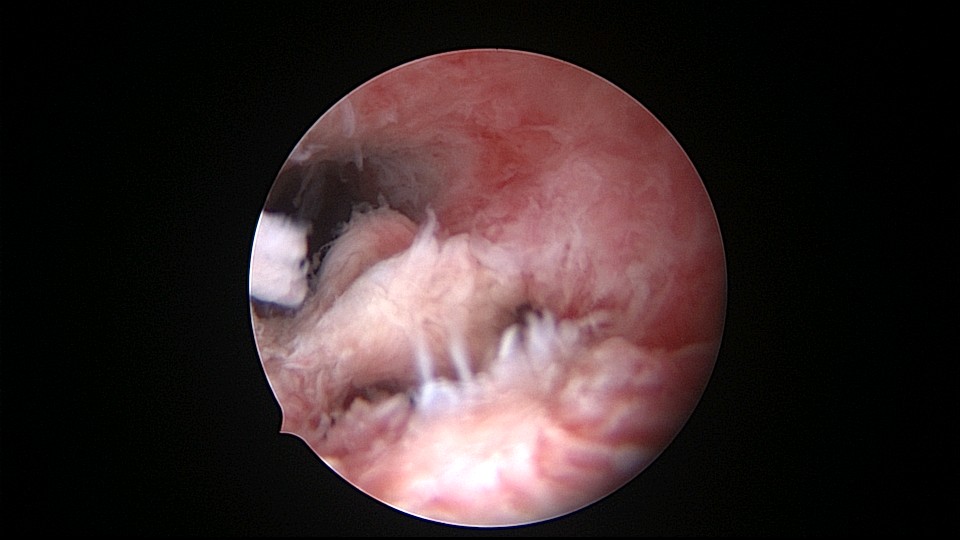

患者48岁,G5P1,剖宫产1次。安环20年,闭经3个月,外院取环失败,形成假道。子宫极度前倾前屈位,宫腔镜见宫颈管上段组织杂乱,左后壁假道,宫腔镜寻找到宫颈内口,艰难进入宫腔,爱母环位置正常,异物钳顺利取出,宫腔无其他异常。